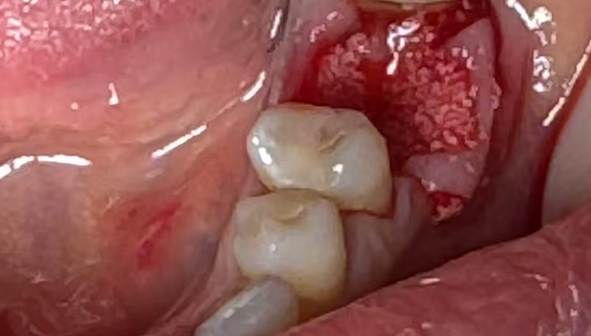

2. A follow-up examination was conducted three months after tooth extraction upon complete wound healing, and implant restoration was initiated.

Post-extraction wound healing status